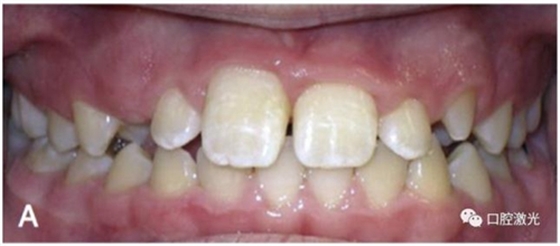

有時,會遇到一些口腔衛(wèi)生問題比較嚴重的患者,從而導(dǎo)致牙齦發(fā)炎而腫大。通過改善口腔衛(wèi)生環(huán)境,炎癥可以得到緩解,但增生的牙齦不一定都可以完全恢復(fù)。下圖的患者就存在口腔牙齦肥厚問題,同時左上部犬牙存在部分萌出的問題,右上部犬牙存在未萌出問題,這些問題都妨礙了托槽的粘接。因此,實施了全口腔的牙齦整形手術(shù)。去除了多余的牙齦組織,增加了犬牙的暴露面積,從而使托槽的粘接更為便利,同時也提升了患者保持口腔衛(wèi)生的狀況。

治療前

激光牙齦整形后即刻

激光治療當(dāng)天粘接托槽

6周后效果